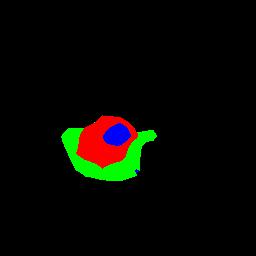

To better retain the deep features of an image and solve the sparsity problem of the end-to-end segmentation model, we propose a new deep convolutional network model for medical image pixel segmentation, called MC-Net. The core of this network model consists of four parts, namely, an encoder network, a multiple max-pooling integration module, a cross multiscale deconvolution decoder network and a pixel-level classification layer. In the network structure of the encoder, we use multiscale convolution instead of the traditional single-channel convolution. The multiple max-pooling integration module first integrates the output features of each submodule of the encoder network and reduces the number of parameters by convolution using a kernel size of 1. At the same time, each max-pooling layer (the pooling size of each layer is different) is spliced after each convolution to achieve the translation invariance of the feature maps of each submodule. We use the output feature maps from the multiple max-pooling integration module as the input of the decoder network; the multiscale convolution of each submodule in the decoder network is cross-fused with the feature maps generated by the corresponding multiscale convolution in the encoder network. Using the above feature map processing methods solves the sparsity problem after the max-pooling layer-generating matrix and enhances the robustness of the classification. We compare our proposed model with the well-known Fully Convolutional Networks for Semantic Segmentation (FCNs), DecovNet, PSPNet, U-net, SgeNet and other state-of-the-art segmentation networks such as HyperDenseNet, MS-Dual, Espnetv2, Denseaspp using one binary Kaggle 2018 data science bowl dataset and two multiclass dataset and obtain encouraging experimental results.